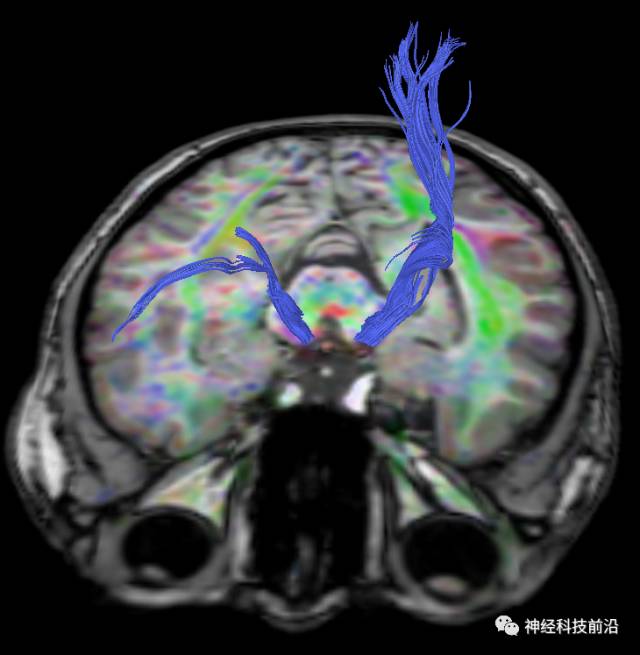

下面为皮质脑桥束的走形方位

皮质脑桥束与脑干高信号(黄色)纤维束

终上所述:脑干高信号为一近环形纤维束,内囊后肢高信号为皮质脑桥束,皮质脊髓束在中脑位置略靠后。高信号位于中脑前缘,是皮质脑桥束的位置所在,另外有部分桥连纤维。